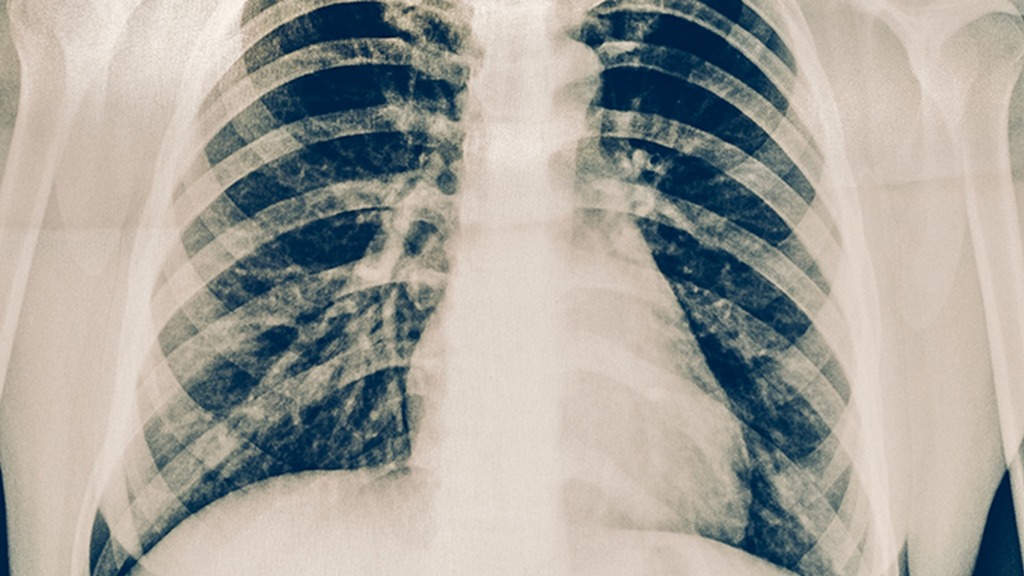

常规胸片为何成了"漏网之鱼"

1.分辨率局限性

普通X光就像隔着毛玻璃看风景,1厘米以下的结节很容易与血管影重叠混淆。而早期肺癌往往以直径5毫米以下的磨玻璃结节悄悄潜伏,等它长到能被胸片识别时,早已错过最.佳干预时机。

2.盲区死角

心脏后方、膈肌顶部,这些被医学影像学称为"隐匿区"的地带,恰好是胸片拍摄时的天然死角。据统计,约15%的肺部病灶会完美躲过胸片"扫射"。